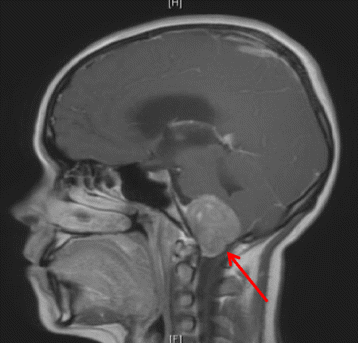

Patient A is a 17-year-old female with extended oligoarticular JIA who presented with symptoms of dysphagia, hoarseness, headaches, vomiting and significant weight loss. Physical examination demonstrated left-sided facial weakness, papilledema, ataxic gait, and cerebellar signs localized to the left. Imaging and biopsy investigations revealed a small, vimentin positive, round blue cell tumour suggestive of Ewing’s sarcoma compressing the brainstem (Fig. 1). The patient had previously received etanercept for her JIA. The patient is now deceased.